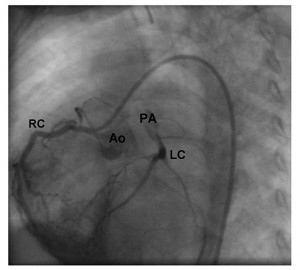

În aceste condiţii sugarul a fost din nou transferat în serviciul de chirurgie cardiacă. S-a realizat cateterismul cardiac care a confirmat suspiciunea ecocardiografică de origine anormală a arterei coronare stângi din artera pulmonară (Figura 5). S-a reintervenit chirurgical. Intraoperator s-a observat originea arterei coronare stângi la nivelul bifurcaţiei arterei pulmonare, posterior, având un trunchi comun destul de lung. S-a realizat implantarea arterei coronare stângi în aortă. Evoluţia post-reintervenţie a fost bună, cu instalarea unei bune creşteri ponderale ulterior. Ecocardiografia a ilustrat noua origine a arterei coronare stângi din aortă (Figura 6), absenţa şuntului la nivelul septului interatrial şi ventriculul stâng revenit la o contractilitate bună (Figura 7); insuficienţa mitrală era uşoara şi persista defectul septal interventricular muscular apical mic. Electrocardiograma s-a normalizat (Figura 8). La 3 ani de la intervenţie copilul este asimptomatic şi are o dezvoltare psihosomatică corespunzătoare vârstei.

Figura 5. Coronarografie: absenţa originii arterei coronare stângi din aortă.

Figura 6. Coronarografie: vizualizarea coronarei stângi prin reinjectare din coronara dreaptă.